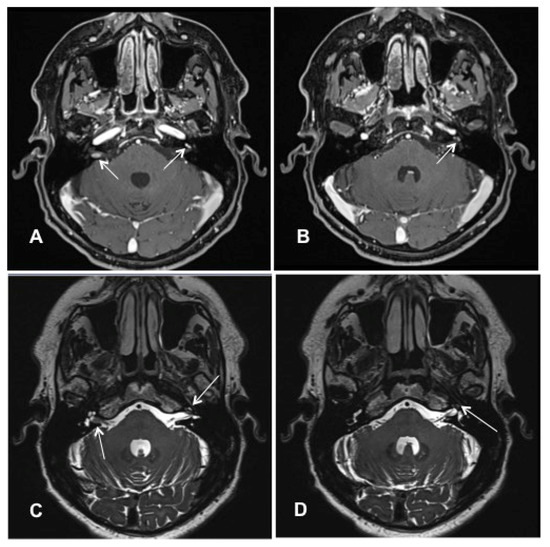

Patient #1 had a vestibulocochlear type of ILS. The tumor extended from the basal cochlear turn towards the vestibulum, ampulla of the superior and horizontal semicircular duct, and the common crus (Figure 2A–D). Tumor resection was performed with an extended round window and a translabyrinthine approach.

Figure 2. cMRI imaging (Case #1). Shown are T1 weighted images with i.v. gadolinium, fat-saturated, 2 mm. The tumor had a vestibulocochlear extension from the basal turn of the cochlea to the vestibulum and ampulla of the superior and horizontal semicircular duct and their common crus. Blue arrow: venous cerebellar malformation. (A) Contrast-enhanced visualization of ILS in the basal cochlear turn (white arrow). (B) ILS in the basal cochlear turn and the ampulla of superior/horizontal semicircular duct (white arrow). (C) ILS in the ampulla of superior/horizontal semicircular duct (white arrow). (D) ILS in the common crus of the superior and horizontal semicircular duct (white arrow).